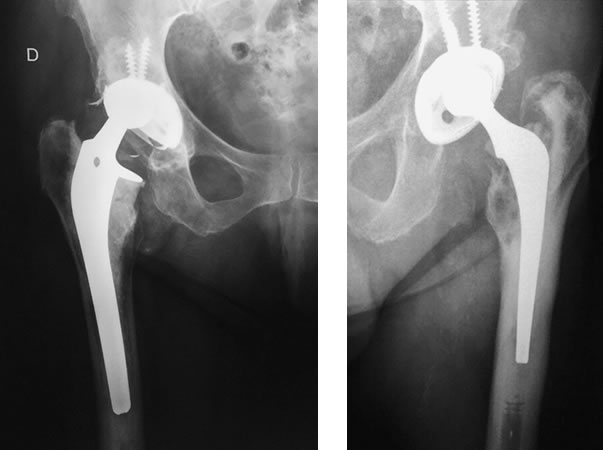

El reemplazo total de cadera es un procedimiento confiable y exitoso para disminuir el dolor y mejorar la función articular. Sin embargo, existen instancias en donde se requiere una revisión del implante. Se refiere a Cirugía de Revisión de cadera a la sustitución de un implante por otro.

La cirugía suele ser mucho más difícil, con resultados no tan satisfactorios como los de la artroplastía total de cadera primaria. La revisión requiere más tiempo quirúrgico, da lugar a pérdida de más sangre y se asocia con una incidencia más alta de complicaciones.

Las indicaciones incluyen: Aflojamiento doloroso aséptico (no infectado) de uno o ambos componentes, fractura o fracaso del implante, Luxación recidivante, artroplastía infectada, fractura periprotésica, etc.

El aflojamiento doloroso de uno o ambos componentes es una complicación a largo plazo. La duración o vida útil de una prótesis de cadera es multifactorial. Los controles traumatológicos así como también los hallazgos radiográficos en el postoperatorio son de gran importancia para el diagnóstico y el tratamiento adecuado.